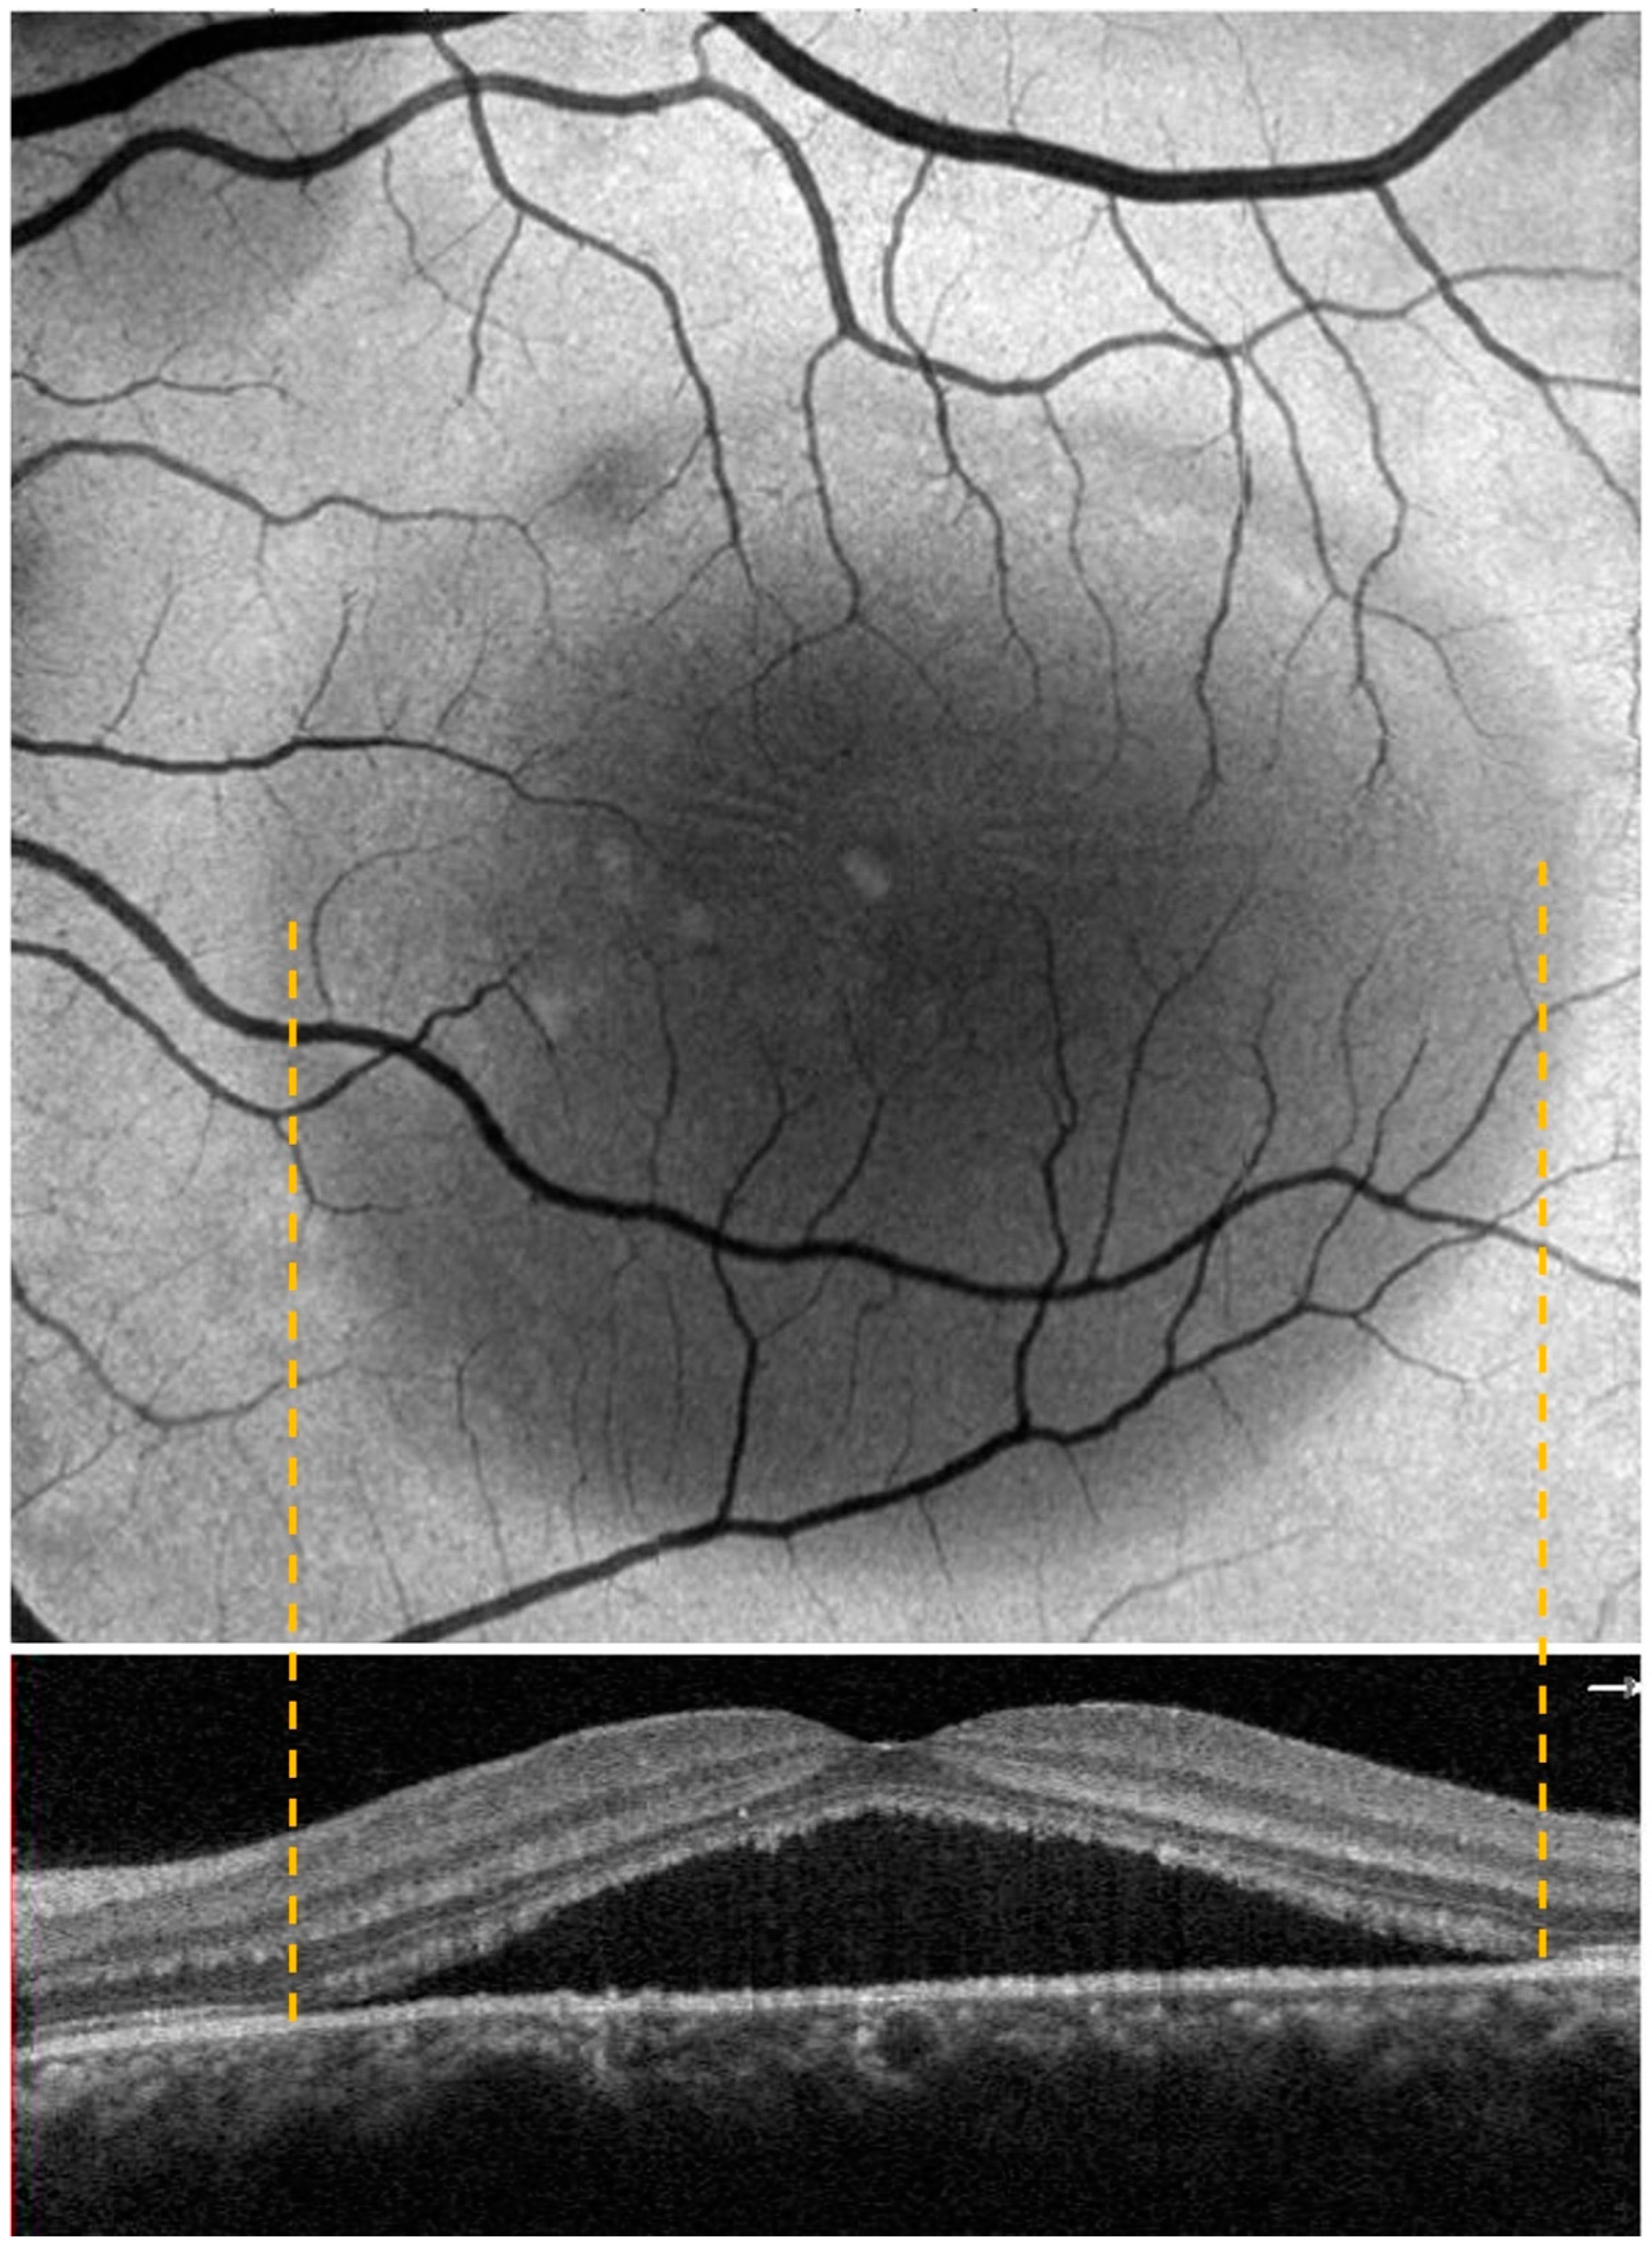

Figure 2.

The figure shows the correspondence between the enface and OCT scan at the CSC edge.

Each patient underwent a complete ophthalmological examination, including best-corrected visual acuity (BCVA), slit lamp examination, dilated fundus evaluation, structural OCT, OCT angiography (OCTA), enface scans (Solix full-range OCT, Optovue Inc., Freemont, CA, USA), fundus retinography (Nidek Mirante, Nidek Co., Ltd., Gamagori, Japan), autofluorescence (blue-light autofluorescence) (Nidek Mirante, Nidek Co., Ltd., Gamagori, Japan), and retromode imaging (Nidek Mirante, Nidek Co., Ltd., Gamagori, Japan) (Figure 1). Each eye was dilated with 1% tropicamide drops before the exams. High-definition OCT B scans (B scan density 512 × 512, 5-micron resolution) were performed centering on the macula region, passing horizontally and vertically through the fovea. The OCTA protocol (Angio-Vue) consisted of a 6.4 × 6.4 mm scan focused on the fovea. This software was provided with motion correction technology, which corrected segmentation errors due to either eye movements or blinks. Once the exam was performed, the OCTA scan, enface image, and corresponding OCT slab were automatically provided by the software in the same printout. We collected enface images at the outer retina level (see the correspondence between enface and OCT scan in Figure 2).